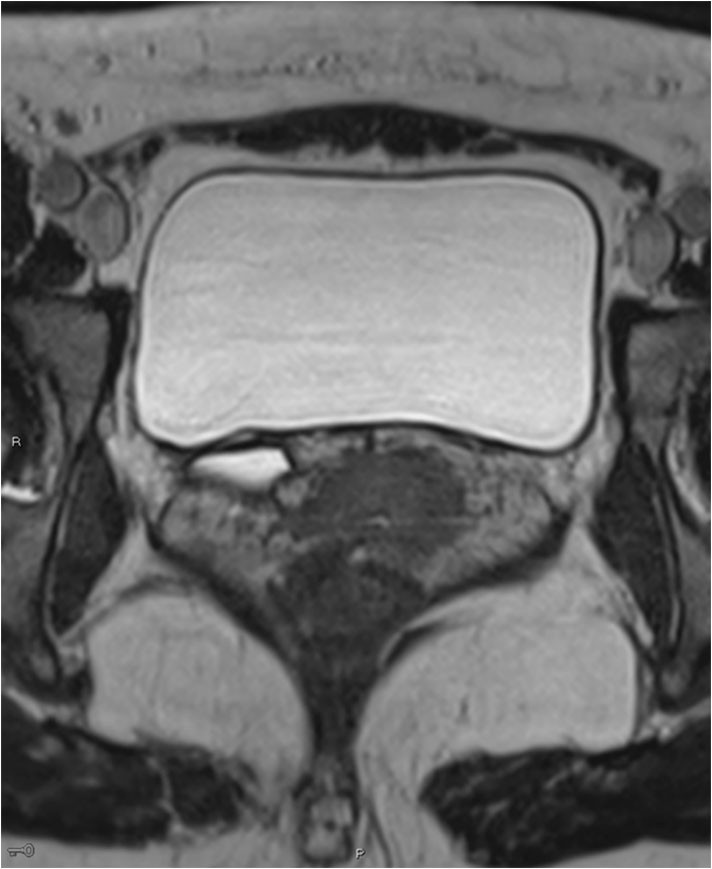

Pasientens tilfelle ble drøftet i et tverrfaglig urologisk team. Renografi viste at begge nyrer var velfungerende. De to anleggene ble vurdert som teknisk vanskelige å skille. Det ble konkludert med at pasienten kunne tilbys operasjon med robotassistert anastomosering av proksimale øvre ureter mot ipsilaterale proksimale ureter. Denne løsningen ble vurdert som fordelaktig med tanke på å bevare nyrefunksjon samt for å minimere risiko for skade på nedre anlegg. Man ønsket å legge anastomosen så kranialt som mulig, på ureter/nyrebekken, der diameter på korrekt forløpende anlegg var god og risikoen for stenose derfor mindre. Peroperativt fant man at nyrebekkenet lå dypt og vanskelig tilgjengelig. Det ble derfor lagt anastomose mot proksimale ureter (fig 4).Det ble lagt to JJ-stenter, en til øvre og en til nedre anlegg (fig 5).

Pasienten hadde postoperativt mye plager fra JJ-stentene. Hun ble også reinnlagt på urologisk avdeling etter 14 dager med en pyelonefritt, som ble behandlet med antibiotika. Nyrefunksjonsprøver var hele tiden upåfallende, med kreatinin 47 µmol/l (45–90). Fire uker etter operasjonen ble stentene fjernet, og plagene forsvant.

Ved postoperativ tremånederskontroll var urinlekkasjen borte. Hun kunne merke litt mukøst sekret i trusen om morgenen. Man antok at dette kunne være fra gjenværende distale ende av ektopisk ureter og vurderte at symptomene ikke krevde ytterligere tiltak. Hun opplevde noe ømhet i høyre flanke, som ble vurdert som en postoperativ muskulær plage. Likevel ble det rekvirert CT urografi for å vurdere postoperativ status. Undersøkelsen viste, som ventet, ingen kontrast i ureter fra øvre anlegg, men normal utskilling via nedre ureter til urinblæren. Det var ingen tegn til hydronefrose (fig 6).